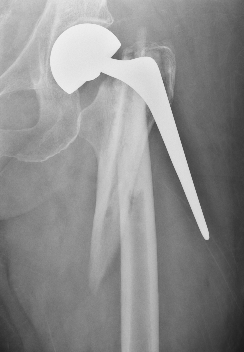

Fracture with stem subsidence around a polished tapered femoral stem treated with ORIF